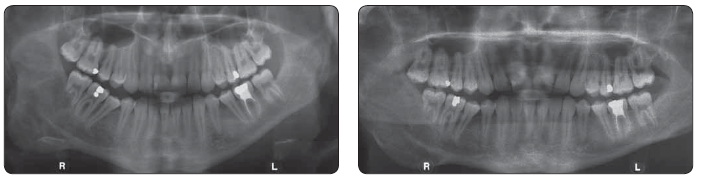

Na naše oddělení byl odeslán 15letý chlapec s postupně narůstající asymetrií obličeje v oblasti pravého úhlu dolní čelisti. OPG a CT vyšetření odhalilo deformaci čelisti, resorpci kortikalis a kořenů přilehlých zubů. Pomocí histologického vyšetření byla stanovena diagnóza CGCG s klinicky agresivním chováním. Chirurgická terapie by znamenala resekci značné části dolní čelisti s deformací obličeje mladého pacienta. Proto jsme se rozhodli pro konzervativní postup a v celkové anestezii, po perforaci kotikalis na několika místech, celkem 6krát aplikovali ve dvou týdenních intervalech směs triamcinolonu (20 mg/ ml) a Supracainu 4% v poměru 1 : 1. Již po třech měsících bylo patrné zmenšení asymetrie obličeje a na kontrolním OPG a CT po 6 měsících výrazná regrese ložiska s novotvorbou kosti. Pacient je nadále sledován a předpokládá se úplné vyhojení tumoru.